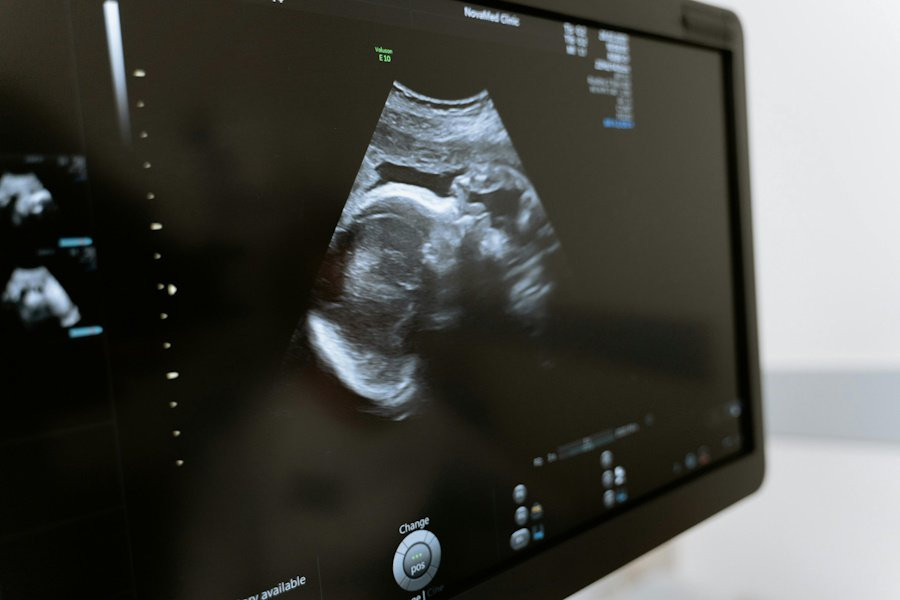

Эксперты изучили данные о 863 017 одноплодных родах, из которых 806 приходилось на гестационных носителей — так называют женщин, вынашивающих детей для других людей. Результаты исследования оказались тревожными: вероятность тяжелых материнских заболеваний среди суррогатных матерей составила 7,8%. Это более чем в три раза выше, чем у женщин, зачавших ребенка самостоятельно, и почти в два раза выше по сравнению с женщинами, прошедшими процедуру экстракорпорального оплодотворения (ЭКО).

Наиболее распространенными осложнениями у суррогатных матерей стали:

- Тяжелое послеродовое кровотечение,

- Тяжелая преэклампсия (серьезное осложнение, связанное с высоким артериальным давлением),

- Послеродовой сепсис (инфекция, возникающая после родов).

Кроме того, исследователи отметили, что у детей, рожденных суррогатными матерями, был несколько выше риск тяжелых неонатальных заболеваний, связанных с преждевременными родами.

Эти данные подчеркивают важность тщательного медицинского наблюдения за суррогатными матерями в течение всей беременности и после родов.